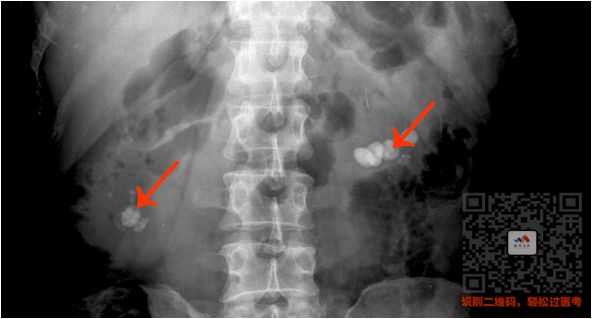

③ 泌尿系统阳性结石

病史:两侧腹部绞痛

特点:

肾和输尿管里面单个或成串的高密度影

看到两侧腹部有白色的圆点

就选肾结石/输尿管结石

看到下腹部的,就选膀胱结石

看图

(双肾结石)

(输尿管结石)

(膀胱结石)